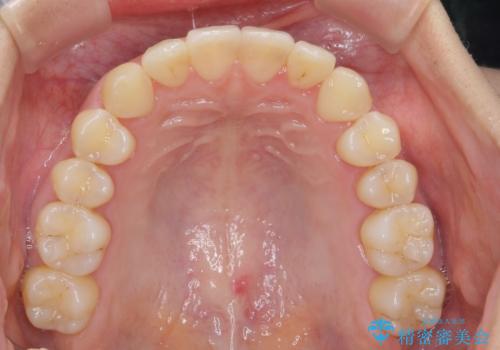

ワイヤー部分矯正治療を併用したマウスピース矯正治療

- 前歯のねじれ、深い噛み合わせ(ディープバイト)の改善を求めて来院されました。

マウスピースでは改善の難しい、歯のねじれ・ディープバイトを部分ワイヤー矯正で改善したのち、マウスピース矯正で全体の歯並びを整えていきます。

部分ワイヤー矯正を行ったことで前歯をしっかりと綺麗な歯並びへと導くことができました。